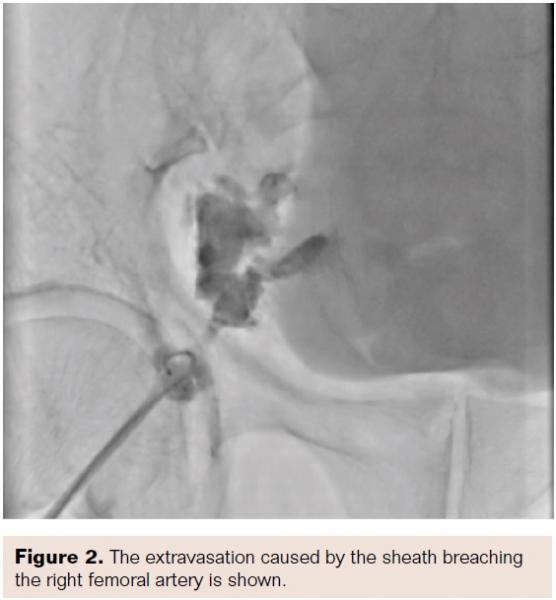

It was noted that the femoral sheath was inadvertently almost out of the body, so it was pushed back into the vessel. However, the patient had severe pain at the puncture site, and a check shot showed that there was extravasation of blood from the femoral artery, out of the sheath into the subcutaneous plane (Figures 1 and 2). The patient had severe hypotension, so although we called the vascular surgeon, we thought we should tackle this by endovascular means.

The sheath in the right femoral artery was retained. A puncture was made in the left femoral artery, and a sheath and a 6 Fr RCA catheter was placed in the right external iliac artery; repeat injection showed continued extravasation through the dissection in the common femoral artery (CFA). An exchange-length guidewire was placed in the dissection, and a peripheral balloon was tracked over this and the balloon was inflated over the perforation for 4 atm for 10 minutes (Figure 3). A second check shot showed the extravasation continued. Then, a 0.014˝ BMW guidewire was passed through the femoral access into the extravasation aneurysmal sac.